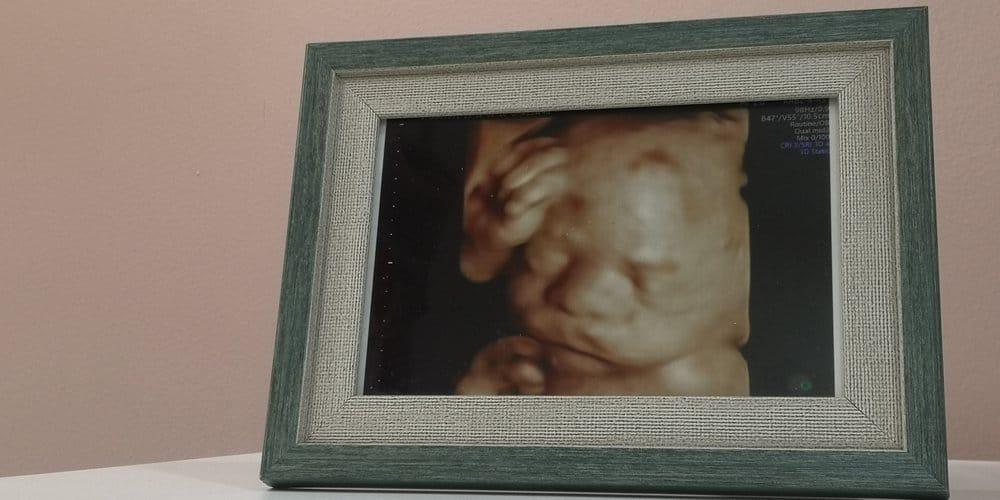

Siêu âm 5D còn được gọi là siêu âm HD, đây là công nghệ siêu âm sử dụng phần mềm xử lý ảnh có độ phân giải cao và tạo cho bức ảnh có tông màu da thịt để làm cho hình ảnh của thai nhi trông giống một đứa trẻ hơn. Vậy bạn nên siêu âm 5D khi nào? Siêu âm 5D có thể được thực hiện từ tuần 24 đến tuần 32 của thai kỳ.

Thực tế, siêu âm 5D tương tự như 3D hay 4D vì chúng ứng dụng cùng một công nghệ, cùng một quá trình quét. Điểm khác biệt duy nhất giữa ba loại siêu âm này là quá trình xử lý hình ảnh, công nghệ càng cao, ảnh sẽ càng sắc nét.